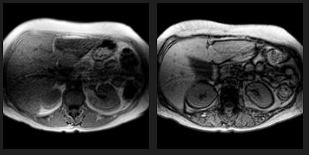

O melhor método de avaliação é a __ (TC/RM).

A

RM.

Perda do sinal do fígado em paciente com hemocromatose primária acentuada.

Na TC o achado de aumento da atenuação é inespecífico, encontrado também em diversas outras doenças (uso de amiodarona, sais de ouro, doença Wilson)